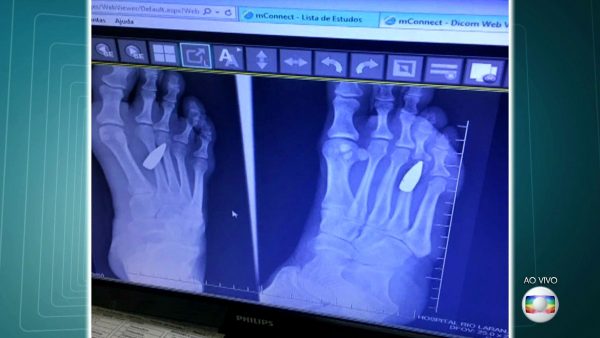

O primeiro atendimento ocorreu na emergência do Hospital Copa D’or. Dispensada após uma sutura simples, procurou outro hospital. o Rio Laranjeiras, onde, a partir de um exame de imagem, descobriu que havia um projétil alojado em seu pé.

Ao avaliar o projétil, o comentarista de segurança pública da TV Globo, Fernando Veloso, afirmou se tratar de uma bala calibre 762, comumente usada em fuzis como o de modelo AK-47- arma de guerra de uso exclusivo das Forças Armadas.